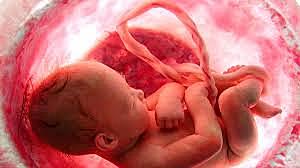

• Placentación

17

Placentación

Se forma l placenta que será el sitio donde se intercambian nutrientes y residuos entre la madre y el feto

• Cordón umbilical

18

Cordón umbilical

Transporta sangre oxigenada y recorre sangre sin oxigeno a la placenta.

Sera el contacto mas directo del feto con el feto con madre, y las acciones que esta realice.